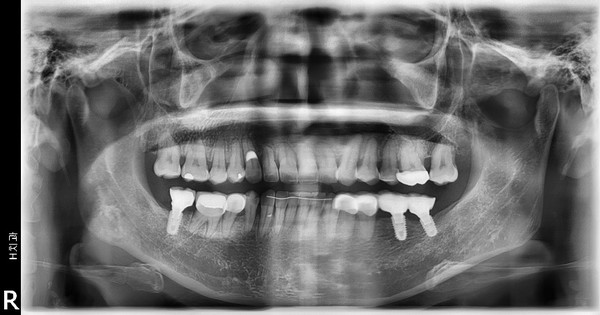

이 환자는 하악우측 제2대구치와 좌측 제1,2대구치가 결손된 환자로 하악 양측 distal cantilever 보철물 하방의 식편압입과 잇몸염증을 주소로 내원하였습니다. 또한 전치부의 crowding을 해결하기 위한 전악교정치료를 원하셨습니다.

하악구치의 cantilever 보철물을 제거하고 temporary crown으로 수복하여 bracket을 부착하였으며 결손부위는 일단 놔둔 상태에서 교정치료를 진행하였습니다.

전치부 decrowding의 영향을 고려하더라도 상하악 전치부의 flare와 동요도가 발생하였는데 이는 대구치부위 posterior support의 부재의 영향이 큽니다.

상악에서 miniscrew를 이용한 2mm 정도의 total arch distalization을 계획하였으므로 상응하는 최종교합형성을 고려하여 하악 대구치부에 임플란트식립을 진행하였고 구치부 support의 조기확립을 위해 temporary crown을 이용한 임플란트 상부보철 진행후 하악치열의 후방이동을 진행하기로 하였습니다.